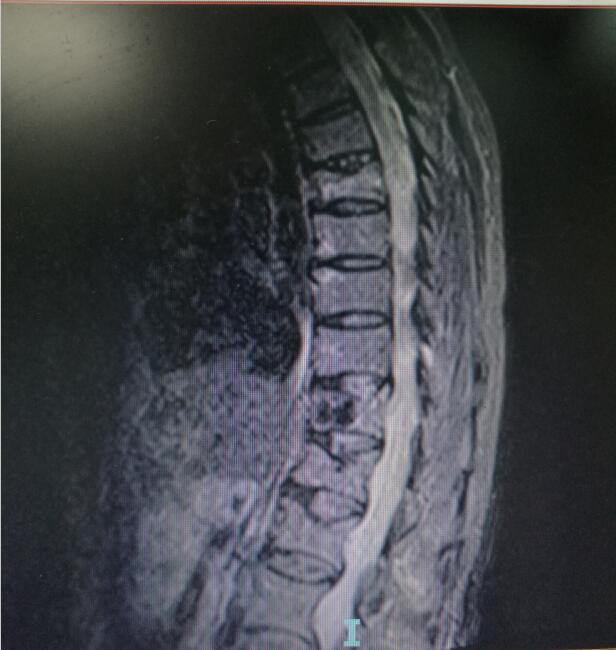

術(shù)前MRI(核磁共振檢查

入院后第四天,由骨傷二科副主任楊陳一、劉永森醫(yī)生、唐國皓醫(yī)生聯(lián)合為患者成功實(shí)施了微創(chuàng)下的經(jīng)皮穿刺椎體后凸成形術(shù)。術(shù)后,患者腰背部疼痛逐漸緩解,術(shù)后第二天即下床活動(dòng)。

“該微創(chuàng)術(shù)式主要針對(duì)中老年患者發(fā)生的胸腰椎壓縮骨折,具有創(chuàng)傷小、恢復(fù)快、術(shù)后第二天即可下床行走等優(yōu)勢,一般患者住院4—5天即可?!碧茋┽t(yī)生表示,考慮到該患者前后兩次骨折均無明顯誘因,背后主要的“元兇”在于其基礎(chǔ)疾病——骨質(zhì)疏松,在治療過程中,除了治療患者的骨折,術(shù)后醫(yī)生還采用院內(nèi)制劑壯筋補(bǔ)骨丸等,積極對(duì)其骨質(zhì)疏松進(jìn)行改善治療,增強(qiáng)其骨密度。經(jīng)過10余天的有效治療,現(xiàn)患者骨折已基本痊愈,骨質(zhì)疏松也得到了一定的改善,于12月12日康復(fù)出院。